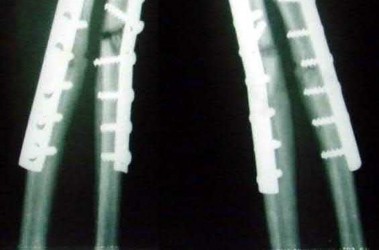

Illustration A shows a heterotrophic non-union of the tibia after intramedullary nailing. The patient was treated with exchange nailing with a larger nail. On the right shows a 4 month post-op radiograph after exchange nailing showing osseous union at the fracture site.